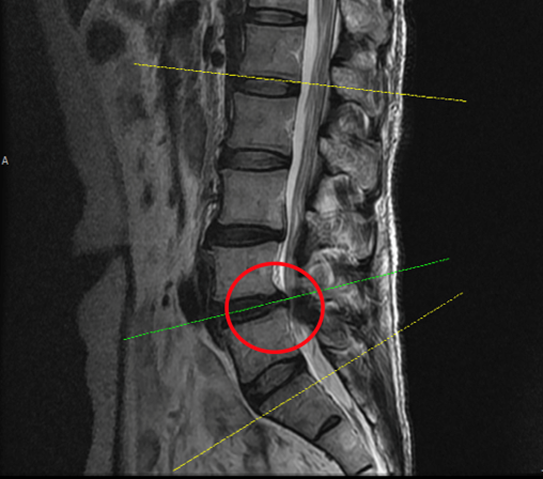

그림2.png 출처: 2025.04.11

<Fig 1. 요추 L4-5번 척추전방전위증>

그때 제 눈에 들어온 건

요추부 4-5번 부위의 미묘한 변화였습니다.

척추 전방전위증과 협착증의 징후가 보였거든요.